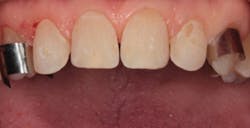

By carefully removing the veneers with fine diamond burs in a high-speed handpiece with water spray, I was able to minimize additional tooth structure removal, and no anesthetic was needed. Figure 3 shows the facial view after removal of the veneers. The incisal view can be seen in Figure 4. The patient decided that she wanted two additional veneers for her second premolars. Final impressions were taken, as well as a facebow record and occlusal registration. The patient chose Vita OM2 bleach shade as her desired color.

Figure 4: Incisal view after removal of the veneers